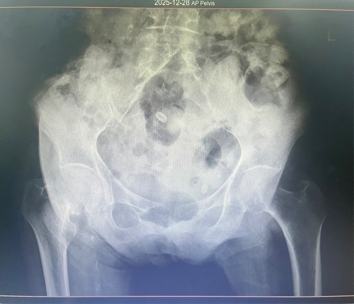

患者为98岁女性,因“右侧股骨颈骨折”入院。此类骨折对老年人健康威胁大,若采取保守治疗需长期卧床,可能引发坠积性肺炎、深静脉血栓、压疮等并发症。因此,尽早手术、恢复行走能力,对改善患者预后具有重要意义。

经过充分准备,李政团队为患者施行“右侧人工股骨头置换术”。手术采用微创方式,力求减少创伤、缩短时间。术中麻醉平稳,出血量少,患者生命体征保持稳定。手术历时约一小时完成。